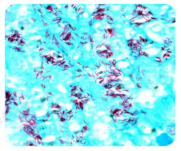

【原理】分枝菌酸与石炭酸复红在加热条件下结合形成稳定复合物,不被盐酸乙醇脱色,故抗酸菌呈红色;非抗酸菌因脂质含量低,易被脱色并被复染成蓝色

【步骤】石炭酸复红加热染色→盐酸酒精脱色→美蓝复染

【结果判断】油镜下观察,抗酸菌呈红色,背景及非抗酸菌呈蓝色